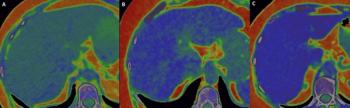

Recently published research revealed that coronary computed tomography angiography (CCTA) exams performed with dual-source CT were completed 22 minutes faster and had a nearly 28 percent higher frequency of good or excellent image quality in comparison to CCTA exams performed with single-source CT devices.